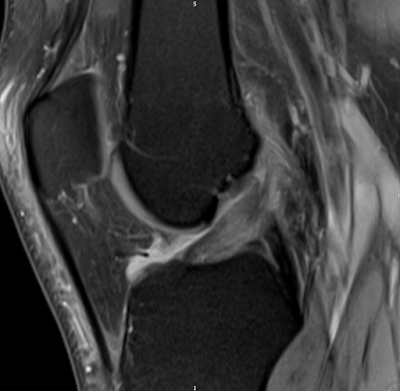

| PD FS Cor: There is a narrow fluid streak between the ACL fibres and the lateral condyle. |